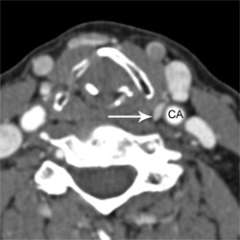

What is a parathyroid 4D CT scan?

Parathyroid 4D-CT represents the latest technology in parathyroid imaging. The resolution of 4D-CT imaging is higher than that of any other type of parathyroid scan. Parathyroid 4D-CT is particularly useful when other imaging studies have been negative (failed to show the abnormal parathyroid gland) or when the anatomy of the neck has been distorted by prior surgery or co-existent thyroid disease. In our experience at UCLA of reading several hundred scans per year, we have been able to detect at least one abnormal parathyroid gland in 99% of cases. In other words, parathyroid 4D-CT is a highly sensitive scan.

A parathyroid 4D-CT needs to be performed at an experienced, high-volume center. we have spent considerable effort optimizing 4D-CT for our patients with challenging parathyroid disease. This process of continuous quality improvement took several years: one year to optimize the scanning technique (2011), another year to validate the results in comparison to actual surgical findings in a standard patient population (2012), and a third year (2013) to validate the results in a more challenging patient population (principally patients who had had failed parathyroid surgery elsewhere who came to us for re-do surgery). More information on parathyroid 4D CT.